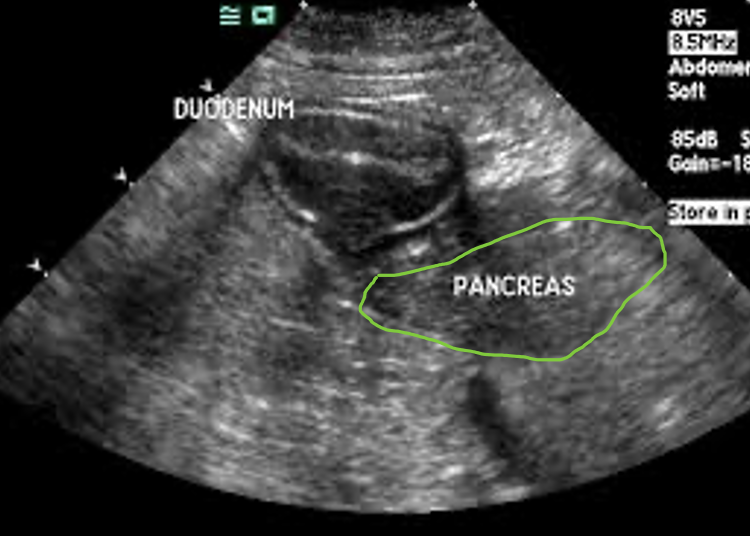

Scanning from the right underside of the patient (patient in right lateral recumbency position), the short axis section of the right limb of pancreas is seen dorso-medial to the ‘coffee bean’ shaped descending duodenum (also seen in short axis)

- From the long axis view identify pyloroduodenal junction in its short axis section

- Rotate the probe through 90°, the small intestine has a prominent ‘coffee bean’ appearance when viewed in short axis and the right limb of the pancreas can be identified in its short axis as a triangular structure situated dorso-medial to the duodenum on the screen.

The short axis section of the right limb of pancreas seen medial and lateral to the descending duodenum (Coffee-bean shape)